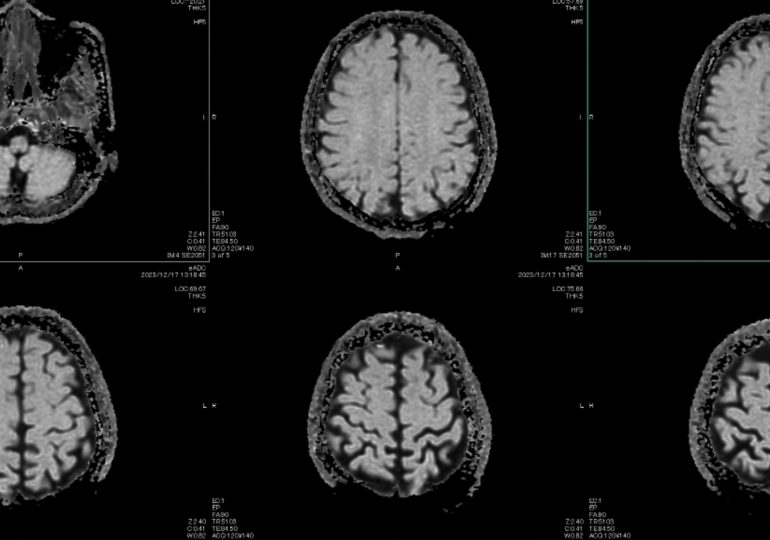

Nearly a decade ago, computer scientist and Nobel Prize-winner Geoffrey Hinton (known as the “Godfather of AI”) said hospitals should stop training radiologists because, within five years, AI would do the job better. Almost 10 years later, there are more radiologists than ever. Of the 950 artificial intelligence and machine learning tools that received FDA approval between 1995 and 2024, 723 were radiology devices. The machines improved. The humans didn’t leave.

The standard question—“Will AI replace doctors?”—turns out to be the wrong one. Demand for healthcare is effectively infinite. There is always another scan to read, another condition going undiagnosed because no one has time to look. AI will not shrink the medical workforce. It will expose how much unmet need was always there.